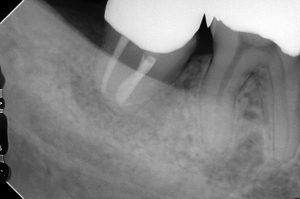

47番(レントゲンの左下奥)が腫れるとのことで受診いただいた患者さんです。

3週間後、根管治療をします。

この時点では全く骨は無いです。

現在、骨もしっかり出来ました。

1、めちゃくちゃ親知らずが深い位置に埋伏しているために抜歯の難易度が以上に高かった。

2、変則樋状根とでも名付けようか、根管形態がかなり変わっていたために、根管治療が難しかった。

先端が90度カーブしてますね。

これは難しい・・・( ;∀;)

しかも一反木綿みたいにウネウネしてます・・・